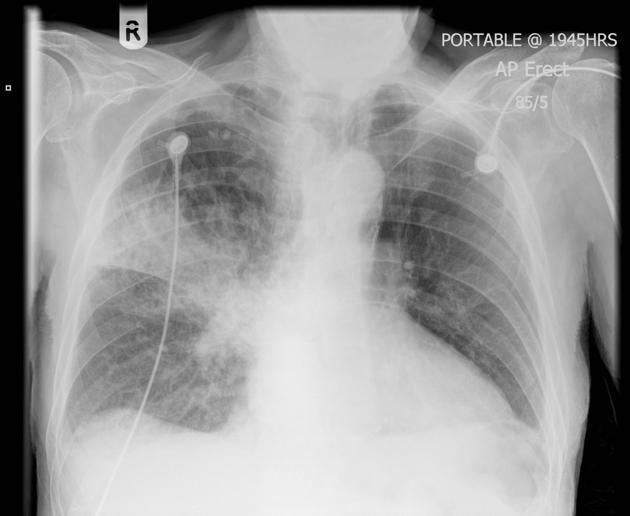

Acute bilateral airspace opacification is a subset of the larger differential diagnosis for airspace opacification. An exhaustive list of all possible causes of acute bilateral airspace opacities is long, but a useful way to consider the huge list is by the material within the airways:

(acute pulmonary edema)

infections, including aspiration-bacterial lung infection, fungal lung, infection

viral lung infection

fluid (put first if big heart)–pulmonary oedema